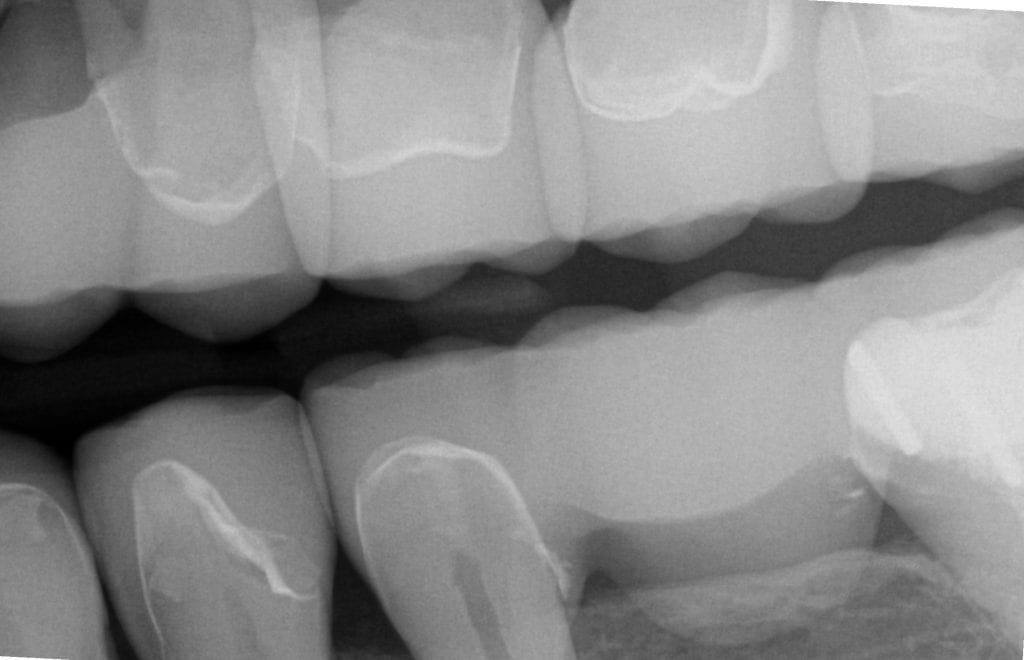

Pre-existing restorations that warranted replacement with an increase in vertical dimension.

Pre-existing restorations that warranted replacement with an increase in vertical dimension. The upper and lower arch were captured with the medit I500 and articulated together with enough clearance to accommodate new restorations and to restore the patient to an ideal tooth position.

ONE WEEK POST-OP RADIOGRAPHS / CEMENT CHECK